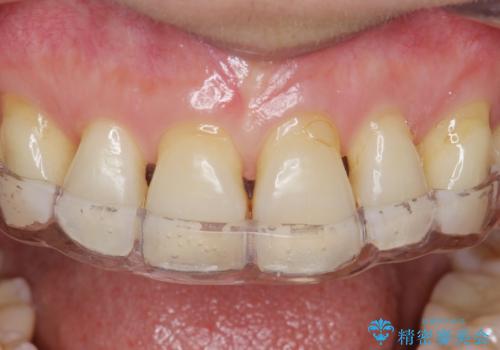

型取り(上下)をして自費のナイトガードを作製しました。

保険のナイトガードと比べると割れにくくて、噛み合わせの歯と調整を行うために歯が変に負担がかかる事なく歯ぎしりや歯の破折を予防することができます。